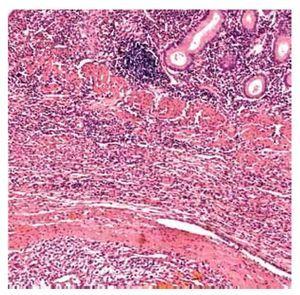

Caso 2. Una mujer de 68 años de edad con historia de nefrectomía izquierda por CaRCC seis años y medio antes del inicio de su padecimiento actual. Fue referida a nuestro Instituto por presentar STDA y dolor epigástrico. La paciente traía consigo un estudio endoscópico que revelaba una neoplasia en la segunda porción del duodeno, del cual no se obtuvieron biopsias. A su llegada se le realizó una tomografía helicoidal (Figura 2) que mostró una masa intraluminal hipervascular en la segunda porción del duodeno. Por este motivo se decidió realizar una PD clásica. La paciente egresó luego de 10 días de estancia intrahospitalaria sin presentar complicaciones. Ha permanecido asintomática y sin evidencia de enfermedad tras 34 meses seguimiento posoperatorio.

¿ Figura 2. Tomografía abdominal con contraste intravenoso en fase arterial, demostrando una masa intraluminal hipervascular en la segunda porción del duodeno. También se observa ausencia del riñón izquierdo.